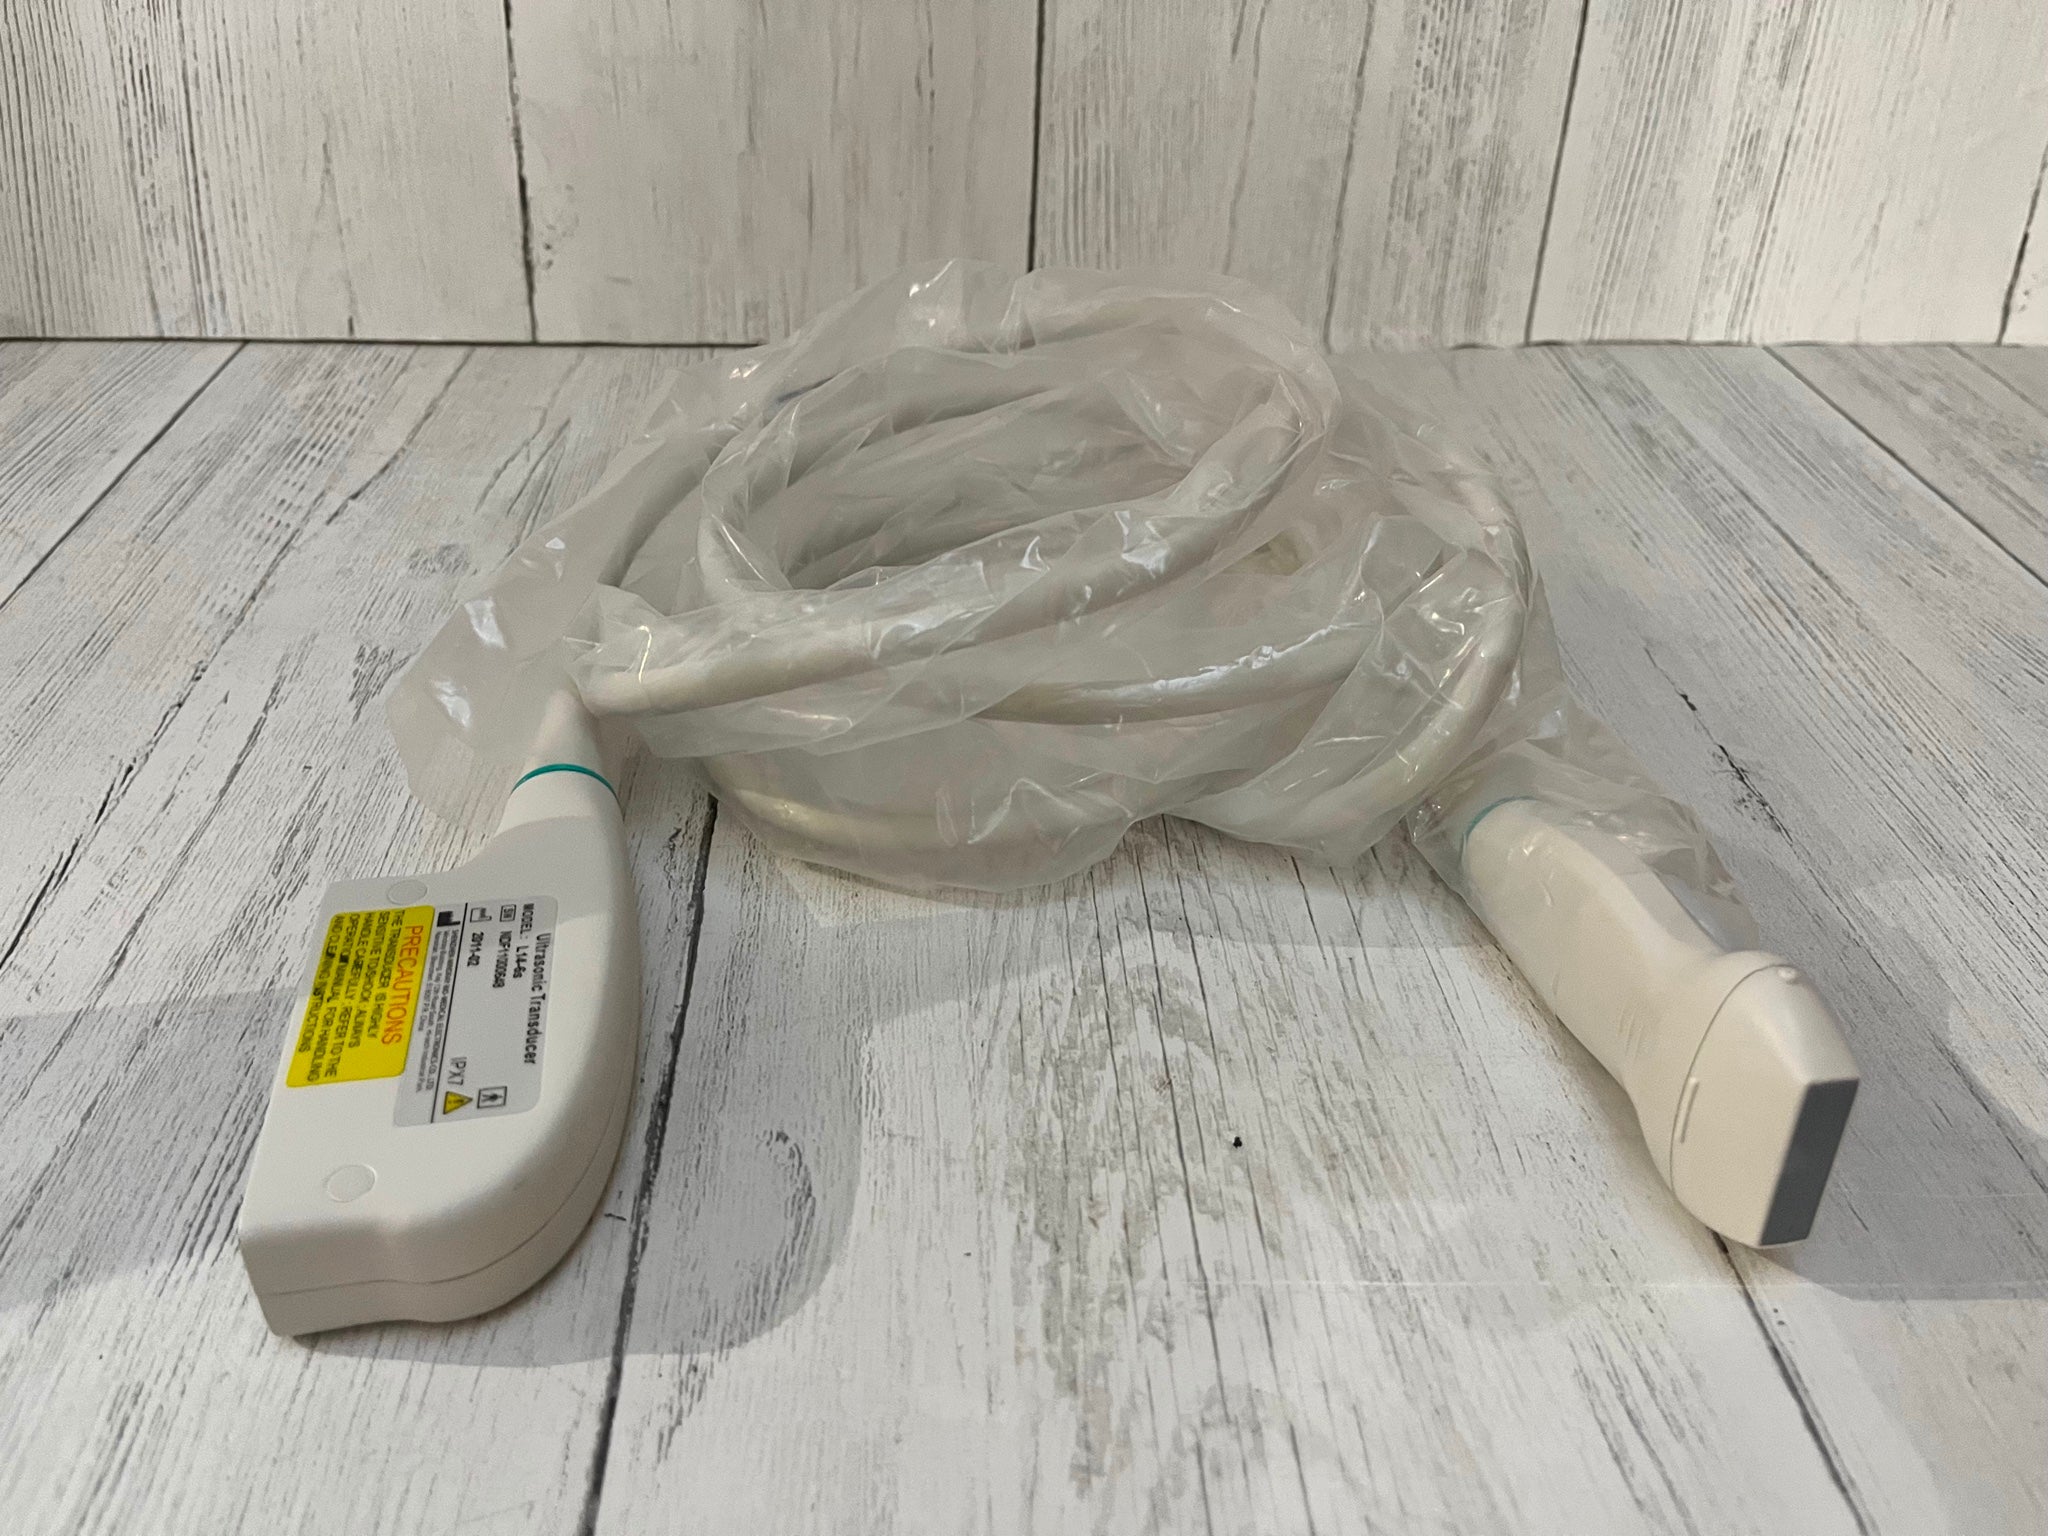

Acuson L382 3.5 MHz Linear Array Ultrasound Transducer Probe.USED TESTED

The Acuson L382 3.5 MHz Linear Array Ultrasound Transducer Probe is a used, tested, and fully functional device designed for high-resolution imaging. Ideal for vascular, musculoskeletal, and superficial tissue assessments, the 3.5 MHz frequency provides excellent detail for imaging of smaller structures. This transducer is compatible with Acuson ultrasound systems and is designed to deliver clear, reliable results for diagnostic applications. Despite being a used unit, it has been thoroughly tested to ensure it meets performance standards. It's a cost-effective solution for healthcare professionals seeking a quality ultrasound probe for detailed imaging.